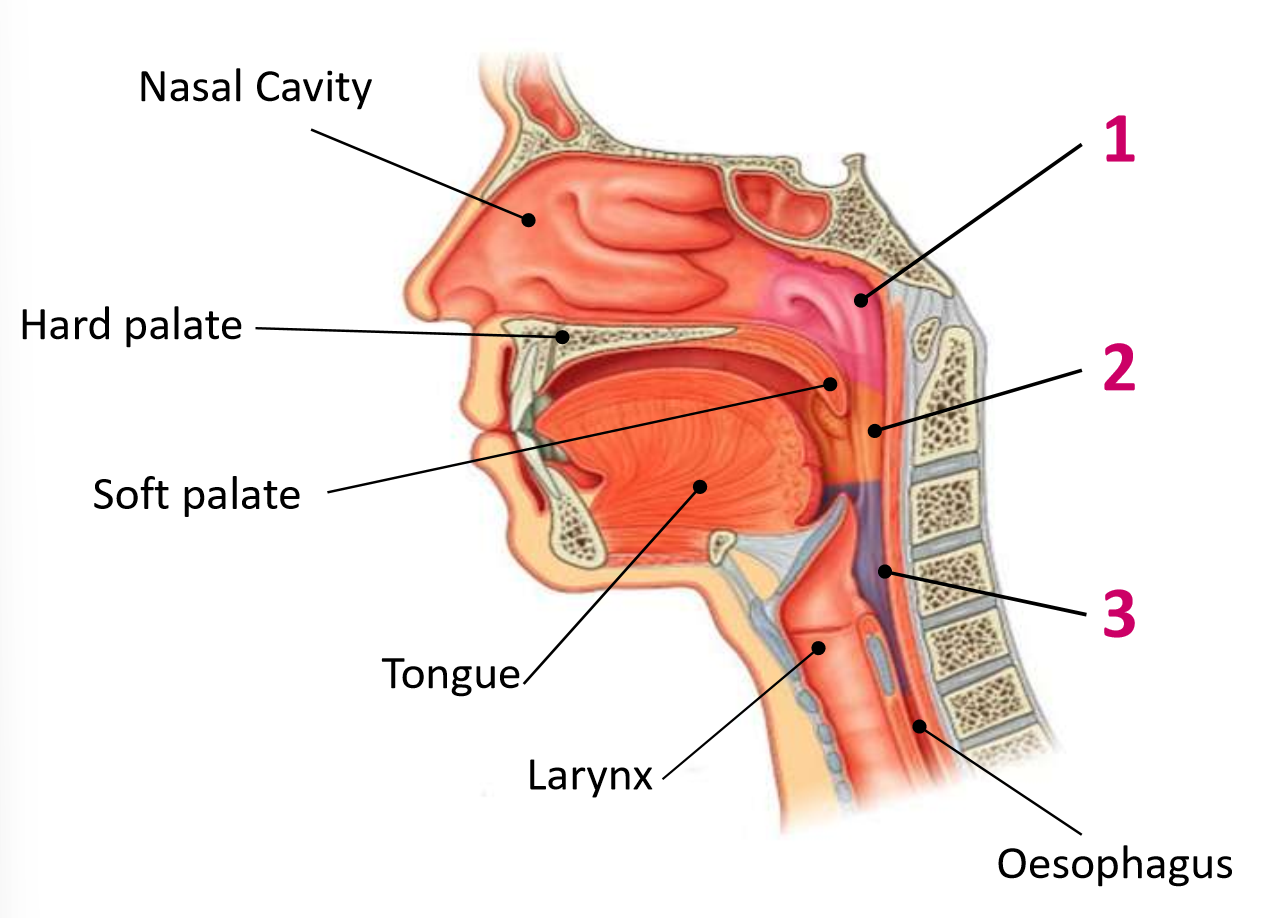

Which area of the head and neck do 1, 2, and 3 make?

pharynx

What region is 1?

nasopharynx

What region is 2?

oropharynx

What region is 3?

laryngopharynx